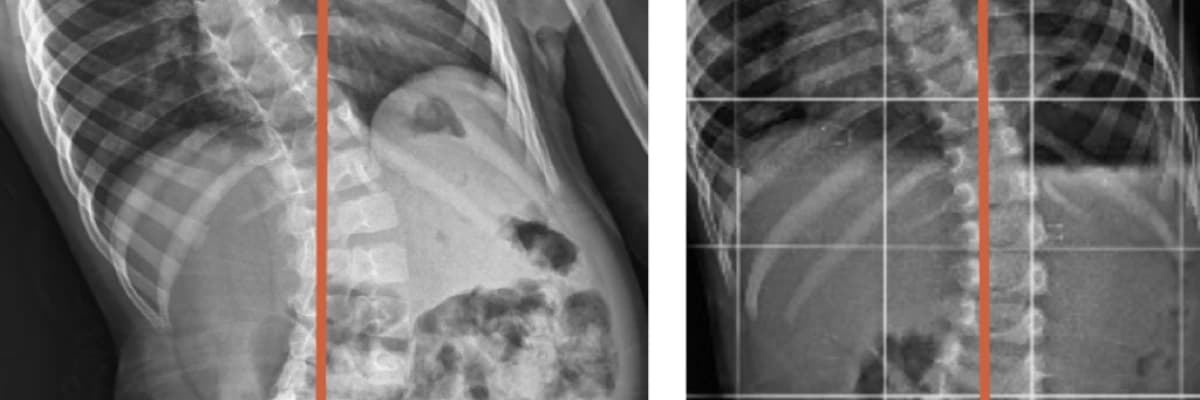

SKOLYOZDA KİŞİNİN HANGİ TÜR SKOLYOZA SAHİP OLDUĞU ESAS ALINARAK O SKOLYOZ TÜRÜNE YÖNELİK VÜCUDU POZİSYONLAYIP EGZERSİZLER VEREREK HAFTADA İKİ VEYA ÜÇ SEANSLA OLDUKÇA HIZLI BİR SÜREDE İLERLEME KATEDİLİR.